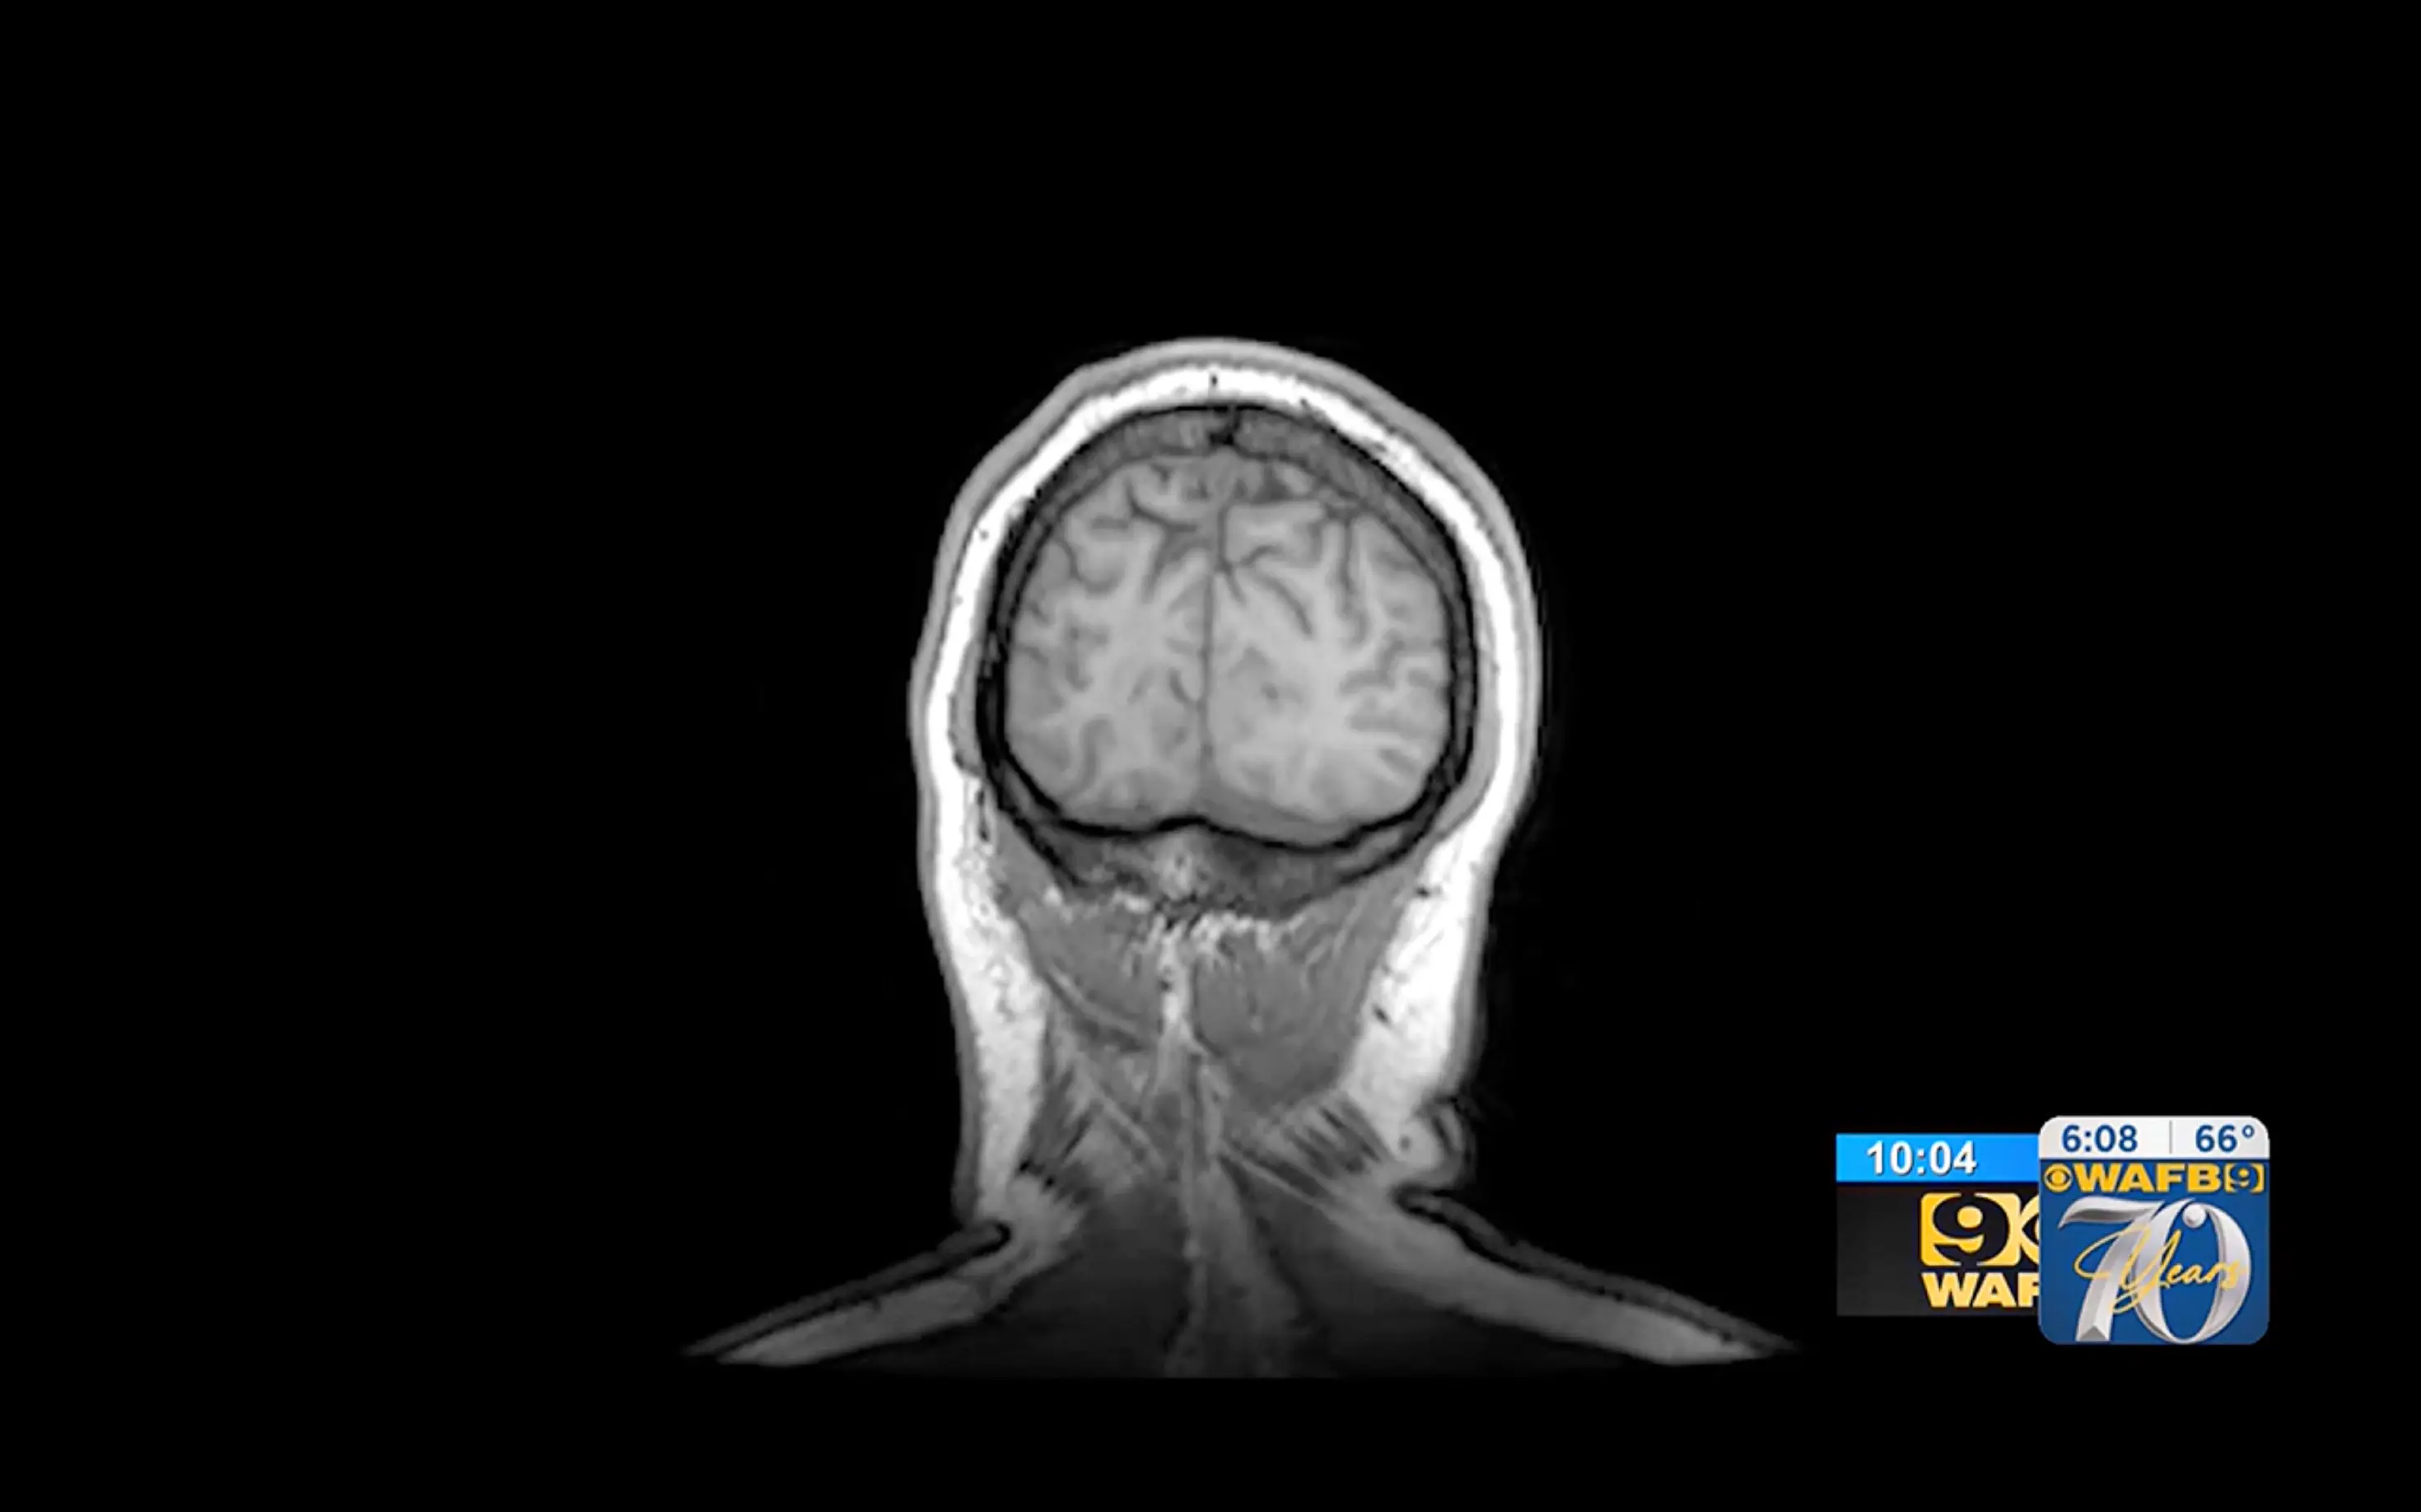

Following the baffling health scare, Denicola was subsequently diagnosed with extensive amnesia, known officially around the world as transient global amnesia, or TGA.

Doctors are still unable to determine the exact cause of her condition, however, despite having carried out extensive tests and scans.